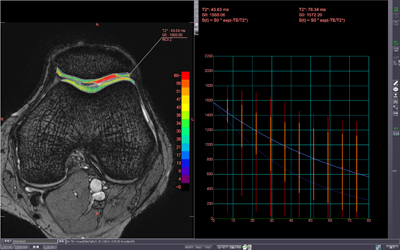

◆Txマッピング

異なるTEで撮像されたデータを利用して,任意に設定したROI内の緩和時間を測定しマッピングするアプリケーションソフトウエアである。T2値やT2*値を測定することで,組織状態の判別に利用できる。TEの時間と信号値の関係をグラフ表示することが可能である。

Txマッピング